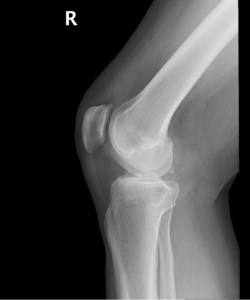

Your doctor will diagnose osteoarthritis based on the medical history, physical examination, and X-rays. X-rays typically show a narrowing of joint space in the arthritic knee.

Osteoarthritis is the most common form of knee arthritis in which the joint cartilage gradually wears away. It most often affects older people. In a normal joint, articular cartilage allows for smooth movement within the joint, whereas in an arthritic knee the cartilage itself becomes thinner or completely absent. In addition, the bones become thicker around the edges of the joint and may form bony “spurs”. All of these factors can cause pain and restricted range of motion in the joint.